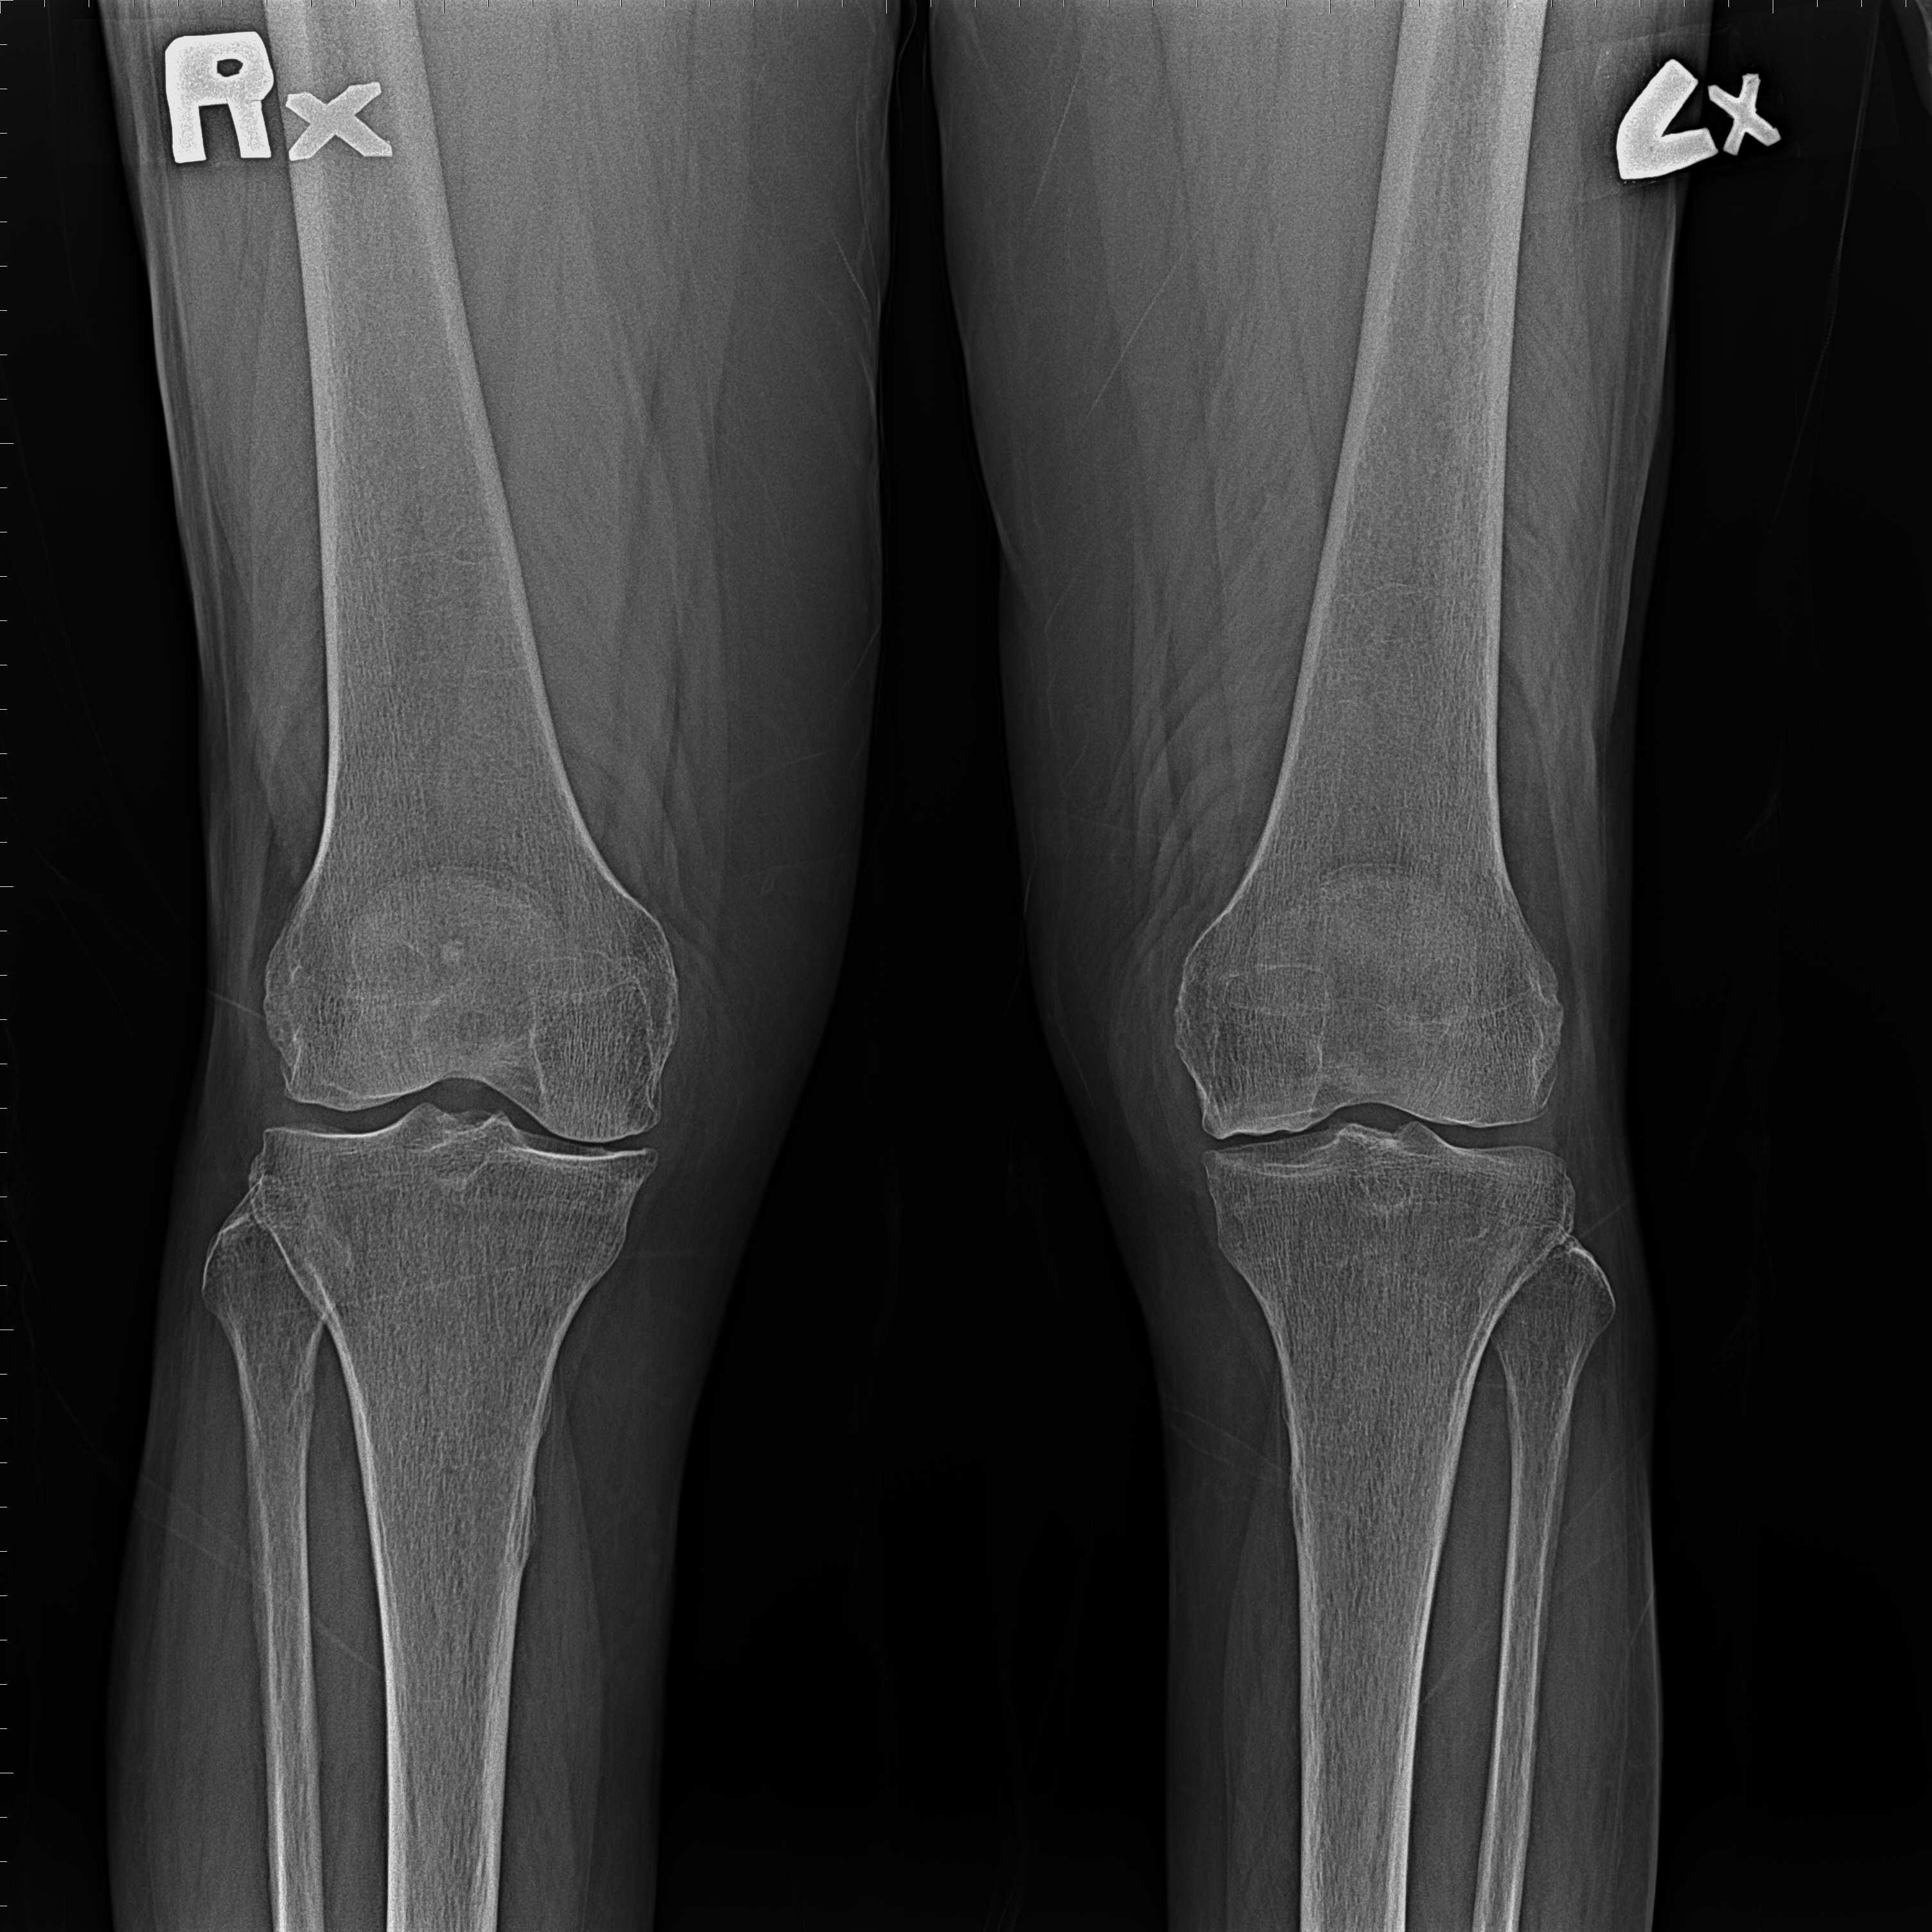

傳統部分膝置換 首頁 案例分享 膝關節手術 傳統部分膝置換 殷女士 65歲 術前 術後 張女士 71歲 術前 術後 蔡女士 74歲 術前 術後 張女士71歲 術前 術後 翁女士70歲 術前 術後 劉女士 80歲 術前 術後